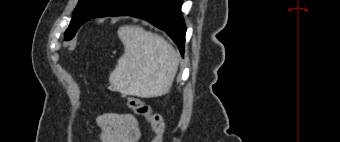

Мультиспиральная компьютерная томография селезенки – высокоинформативный лучевой метод исследования, основанный на использовании рентгеновского излучения и позволяющий детально визуализировать паренхиму селезенки, состояние близлежащих органов и тканей, питающих ее кровеносных сосудов и регионарных лимфоузлов.

МСКТ селезенки проводится как с использованием контраста, так и без него. Контрастирование применяется для выявления патологических очагов, которые могут быть не видны при нативном исследовании. Для этого внутривенно вводится контрастный препарат, содержащий йод и накапливающийся в патологических очагах опухолевой и воспалительной природы.

Мультиспиральная компьютерная томография селезенки с внутривенным болюсным контрастированием используется в диагностике гематологических заболеваний, опухолевых процессов, при планировании хирургического вмешательства и для отслеживания эффективности лекарственной терапии.